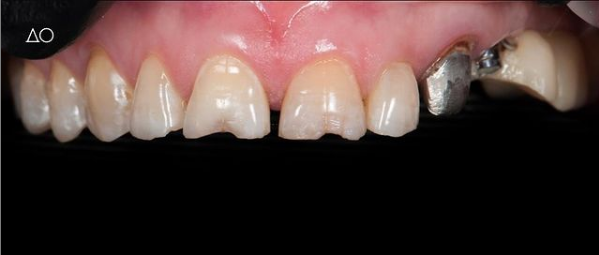

Установка керамической коронки

Доктор: Котиков Илья Сергеевич